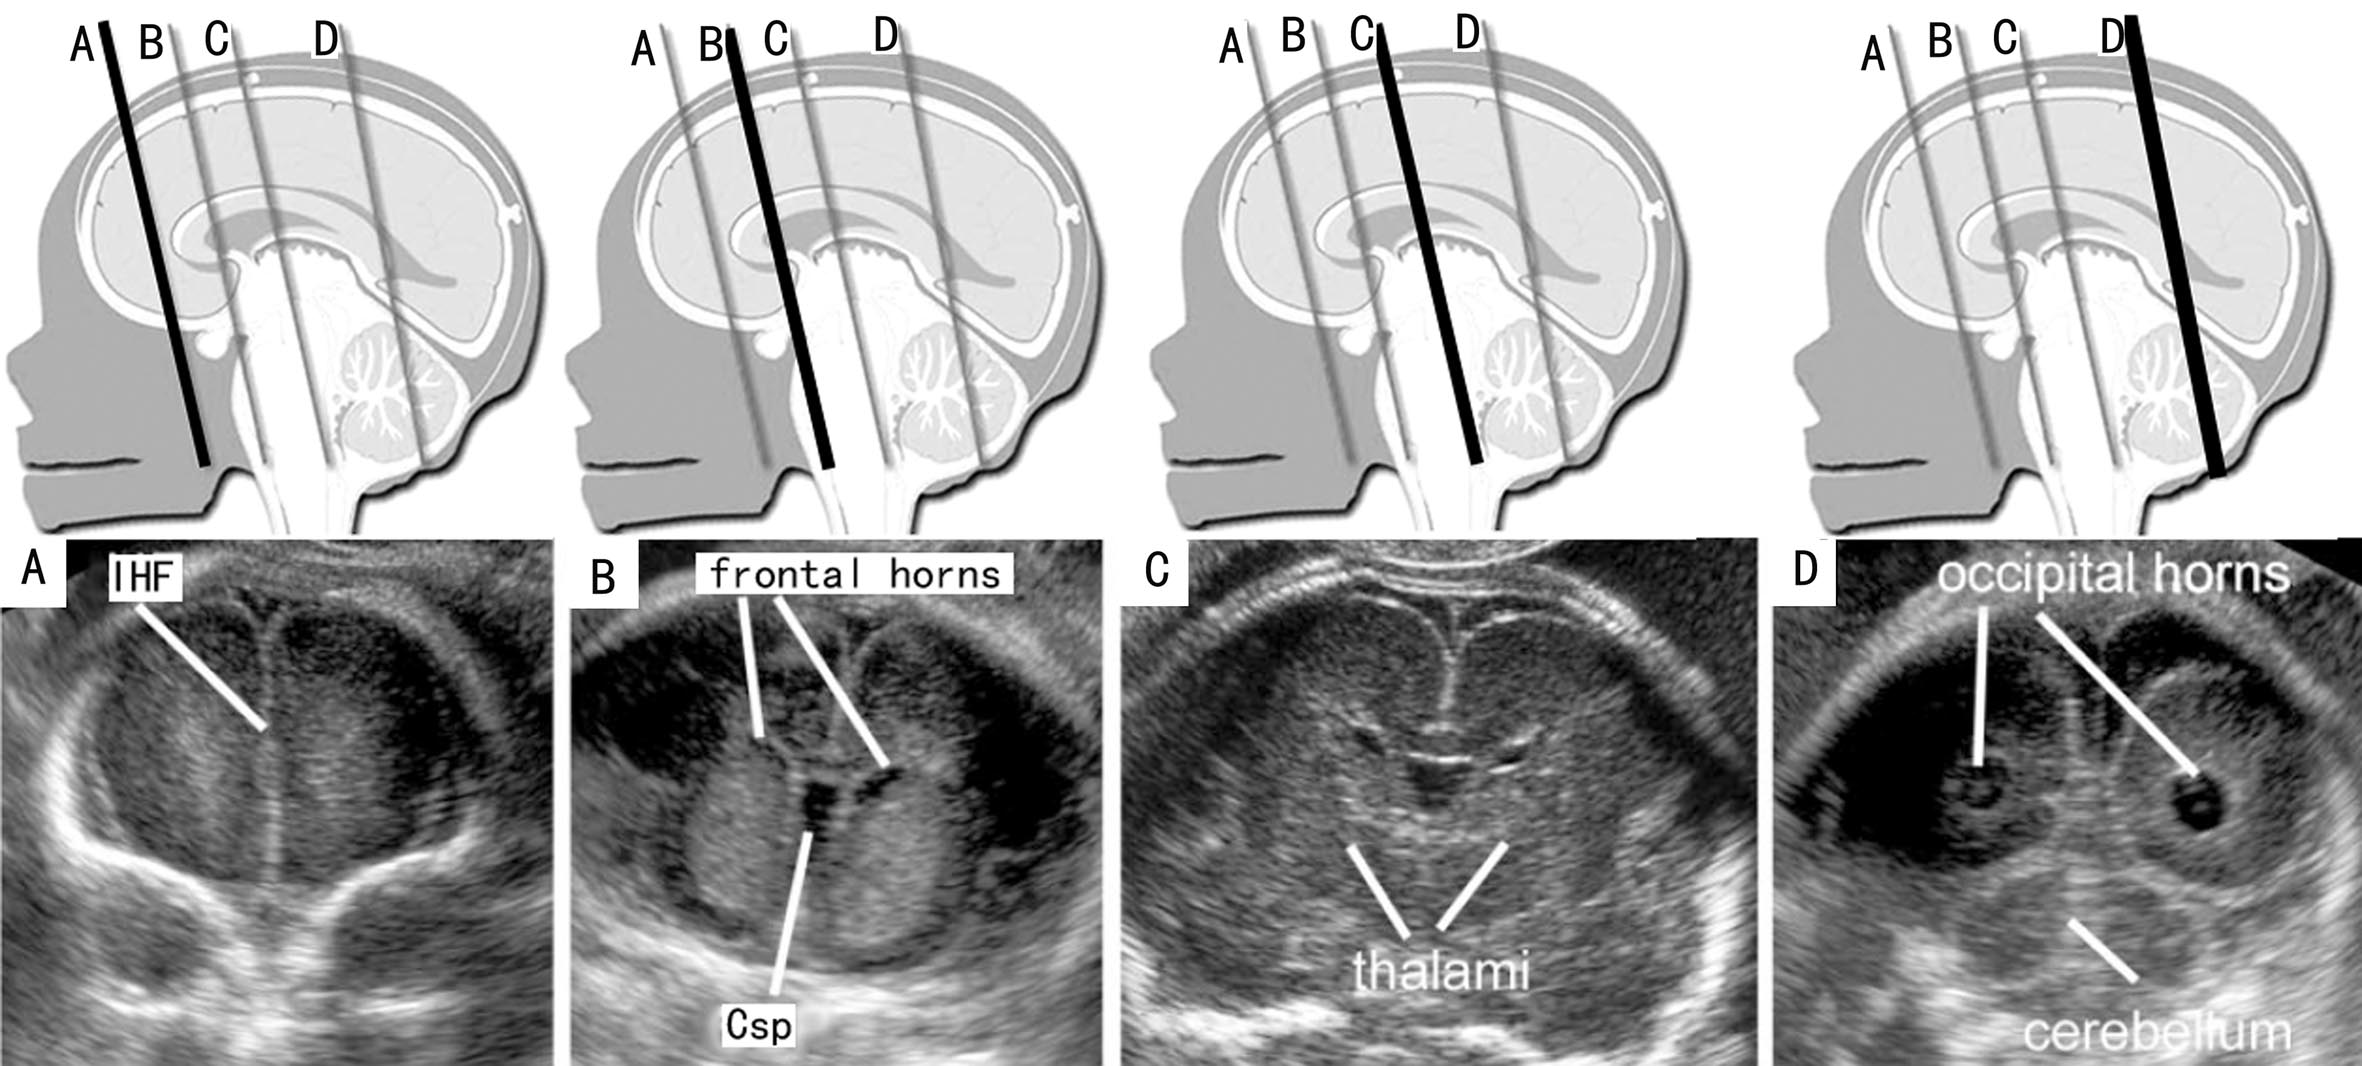

二、冠状面

胎头的冠状面(CP)结构辨认相对困难,在头位时TVU相对容易显示;臀位时或其他胎位时,如果胎头额顶部贴近母体腹侧,则TAU适当调整探头可以显示胎头的冠状切面。

探头与胎儿面部平面平行、由前向后可以显示胎儿头部一系列CP。前额CP显示的结构主要包括中部由大脑纵列形成的强回声及其两侧均匀的大脑额叶,颅顶及侧部显示膨隆的颅骨强回声,颅底两侧稍向颅内对称的膨起由眶腔顶部形成(图7-4A);探头稍向后倾斜可在脑实质中部近大脑纵裂区域显示TV前角,大脑纵裂强回声的上端的三角形无回声为上矢状窦,下部终止于SP的菱形回声上方的胼胝体部膝部,后者显示为连接大脑半球的中等回声;脑实质内由于脑裂和沟回的出现而形成不同的区域和不均匀的回声(图7-4B);偏外下方可见大脑侧裂回声。

探头向后移动近中部CP时可以显示丘脑平面,上述结构仍可见显示,TV体部显示较小,周围的脑实质回声不甚均匀,SP深部的稍强回声为丘脑,大脑侧裂显示更为明显(图10-4C),位于深部中线区域、丘脑稍前方的回声包含颅底动脉环及视交叉等结构;在探头移动过程中有时还可显示第三脑室。探头继续后移显示小脑时称为经小脑平面或枕部平面。比较明显的结构就是TV后角、CP、小脑和小脑蚓部、CM等(图7-4D)。

图7-4胎头冠状面声像图